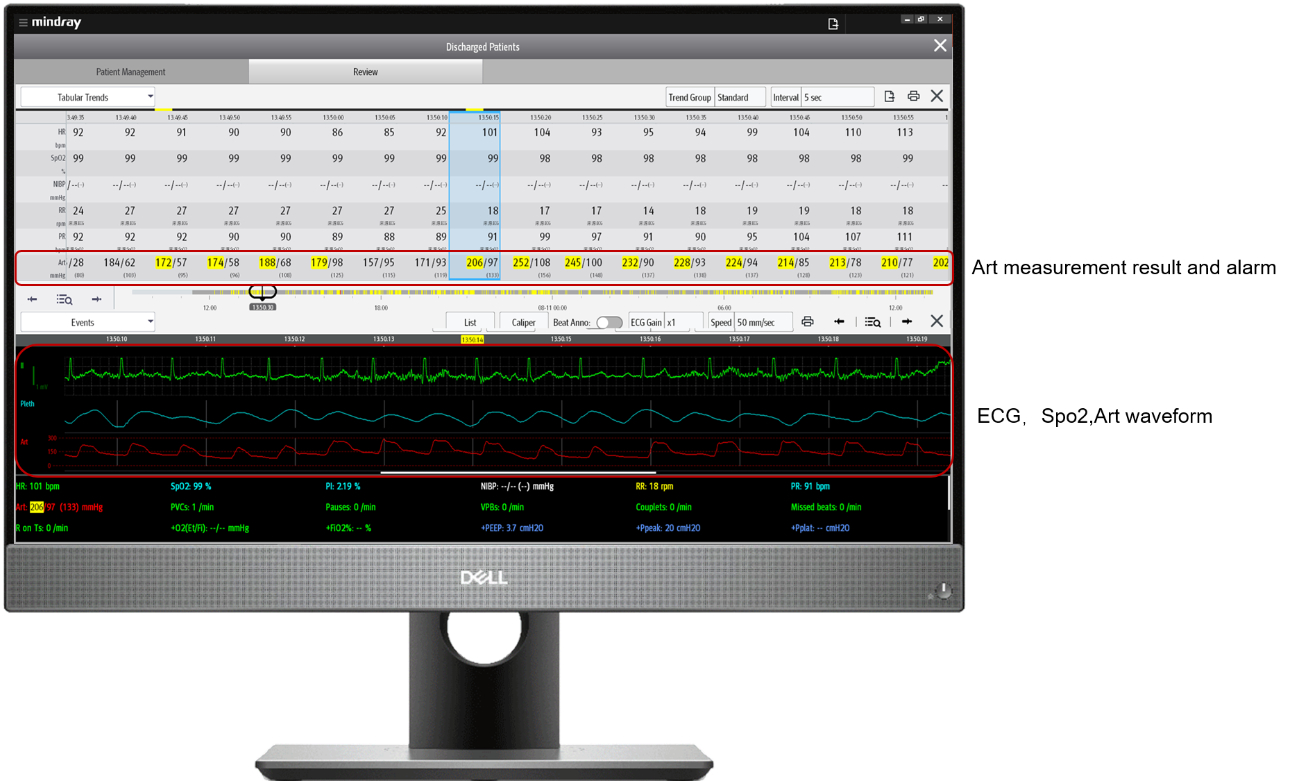

The physician in charge repeatedly received an alarm that the patient's IBP exceeded the limit from the applicationŌĆ£Mobile ViewerŌĆØ in his phone (Figure 2).

Through the Mobile Viewer, the doctor found that the patient presented with multiple episodes of abnormal IBP after admission into hospital. The ECG and SPO2 were normal,?however, the IBP increased up to 207/187 mmHg and dropped to 60/49 mmHg within a few minutes (as shown in Figure 3). The doctor checked both real-time and historical vital signs in the WorkStation. Wondering what caused the multiple dramatic spikes and drops of the IBP?

Daily Case Discussion in the morning: this patient's condition was complicated and given such condition, the director checked the patient's real-time and historical vital signs and discussed inside the team. (As shown in Figure 4)

The vital signs trend table (as shown in Figure 5) shows that the patient experienced multiple dramatic spikes and drops of IBP after admission. Since IBP monitoring is easilyaffected by artificial factors, including blood drawing, tube flushing and bending, it is necessary to exclude the IBP interference and analysis patientŌĆÖ s blood pressure fluctuations, after confirming that it is not caused by interference, they reviewed all the vital signs again and found that multiple over-limit IBP alarms existed in a short period of time.

Doctors checked the full disclosure wave- forms of ECG, SPO2 and IBP, confirming that the sudden deterioration IBP were real phenomenon and happened to this patient. and also the abnormal IBP fluctuations could appear even though there were no adjustment of vasoactive agent and bedside manipulation stimulation.